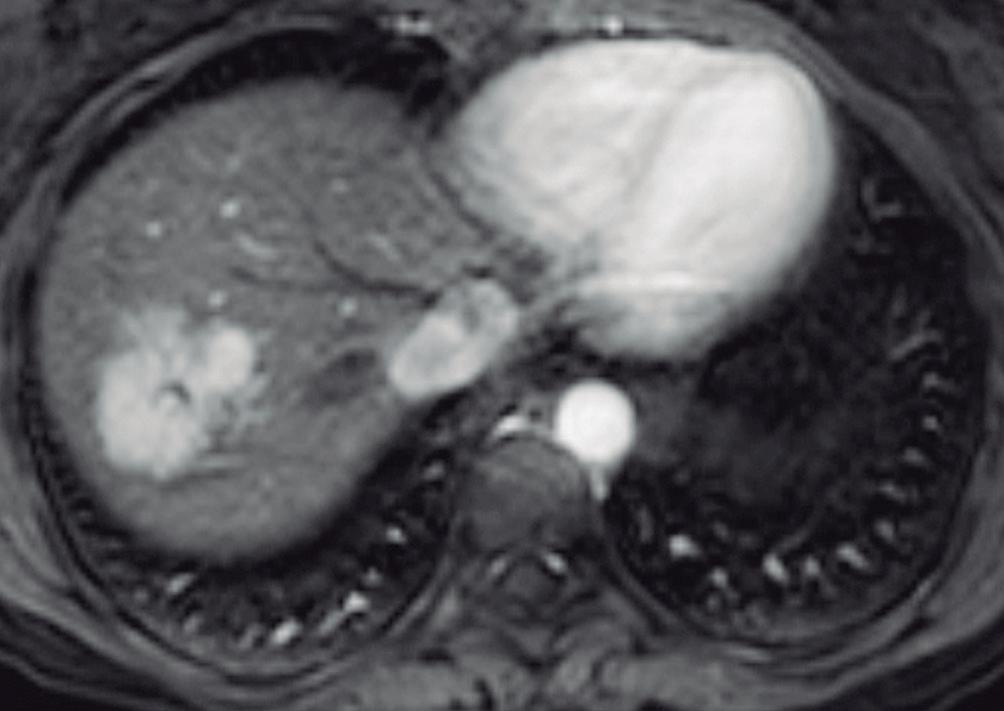

(Figura 1) En los hemangiomas de mayor tamaño el pasaje del contraste al centro de la lesión toma más tiempo e incluso no ocurre en aquellos más voluminosos.

En la RM los hemangiomas son lesiones con señal hipointensa en T1 e hiperintensa muy marcada en T2. Esta última característica los diferencia de otras lesiones benignas o malignas, con excepción de los quistes, que presentan señal más elevada debido a su contenido acuoso.1 El patrón de realce poscontraste es igual al que muestra la TC. (Figura 2) En la secuencia de difusión no presentan un patrón restrictivo, si bien pueden exhibir una señal brillante en valores b altos (parámetro que pondera la difusión); esto se debe al efecto brillo T2 y no a la restricción verdadera, por lo que el mapa del coeficiente de difusión aparente (ADC, por sus siglas en in-

A

glés) muestra señal y valores altos. En estudios con CHE son hipointensos en fase hepatobiliar ya que carecen de hepatocitos. Una potencial causa de error puede ocurrir en algunos hemangiomas pequeños que presenten un refuerzo precoz importante y que en fase de equilibrio (3 minutos) pueden presentarse hipointensos (pseudolavado). De esta manera podrían ser malinterpretados como un CHC.2 No obstante, la característica señal brillante de los hemangiomas en T2 es de utilidad para una tipificación correcta.

A, en fase arterial; B, y en fase de equilibrio; C, que muestran una lesión de contornos lobulados y bordes netos en el lóbulo hepático derecho que presenta refuerzo globular, progresivo e isodenso con las estructuras vasculares.

A: T1 post contraste en fase venosa portal; B, y fase de equilibrio; C: Muestran lesiones en segmentos IV y VI con una señal marcadamente hiperintensa en la secuencia T2 y

Lesiones benignas localizadas en el hígado desde la mirada de las imágenes Mariano Volpacchio Figura 1. Hemangioma en tomografía computada. Imágenes axiales de la TC sin contraste Figura 2. Hemangioma en la RM. Imágenes axiales de la RM en secuencia T2 con supresión grasa con el refuerzo similar a las estructuras vasculares de aspecto globular y progresivo en sucesivas fases. Nótese la heterogeneidad del hemangioma de mayor tamaño en segmento VI. A B C